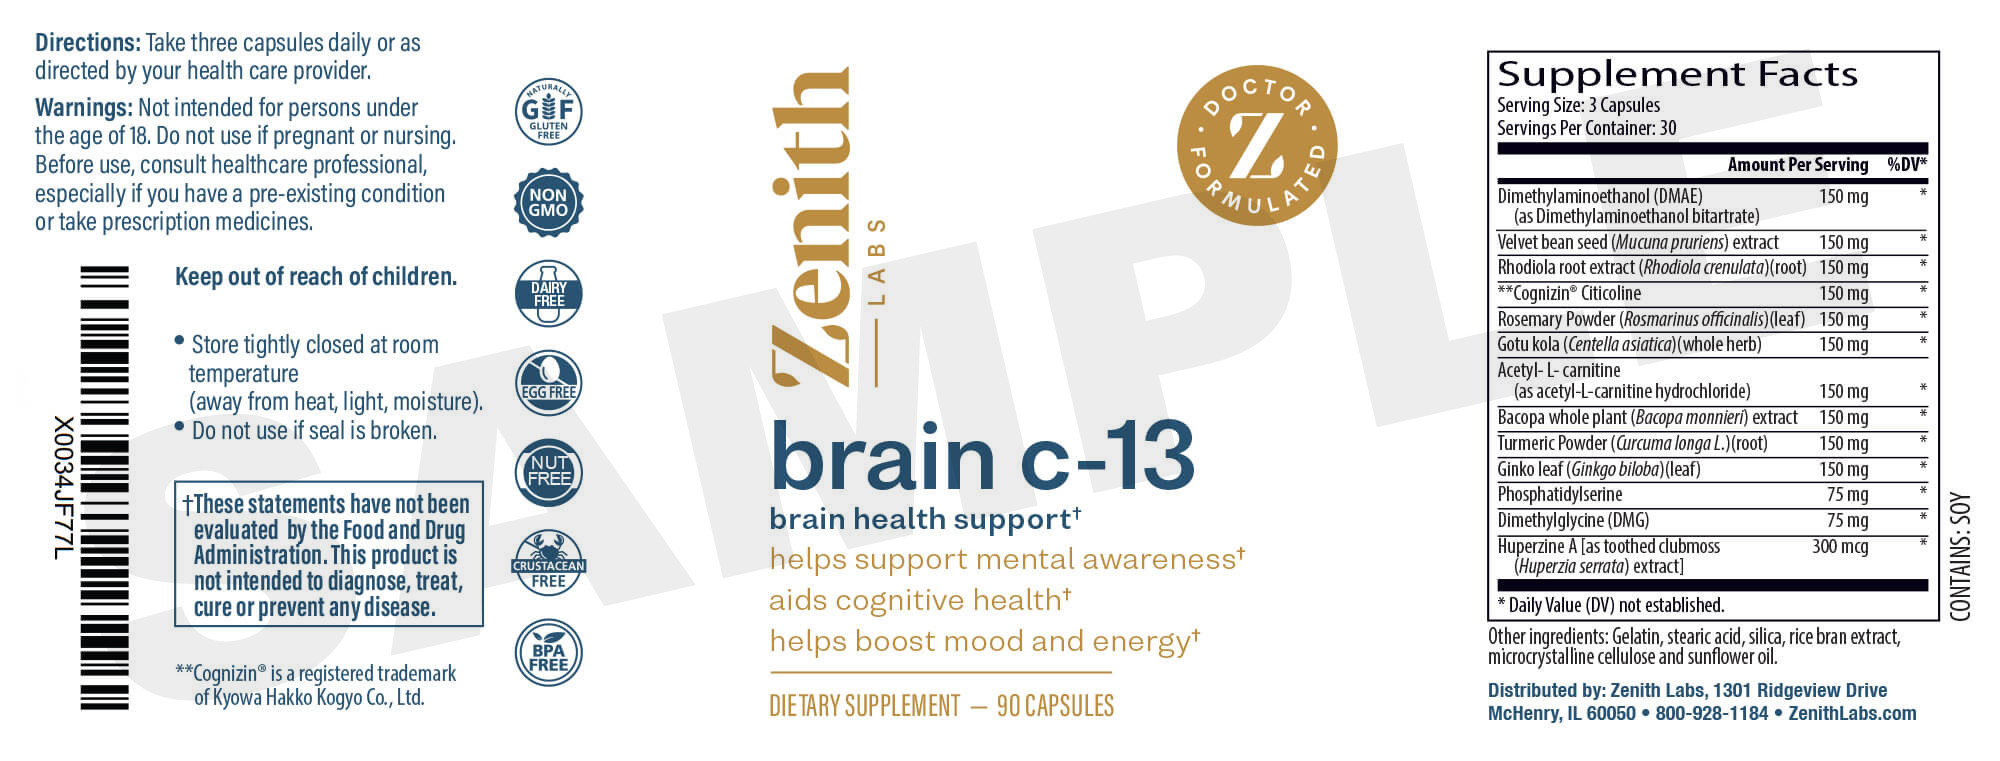

Zenith Labs® is in a unique position to help...

We've built a reputation for finding innovative health solutions in nature, that are backed by solid research.

And with that reputation, we've built industry relationships that allow us to find and source premium nutrients that aren't available in most stores.

We've created a simple way

to get enough citicoline.

It supports a healthy memory, and a quick, sharp mind…

…because it repairs your Mental Powerlines.